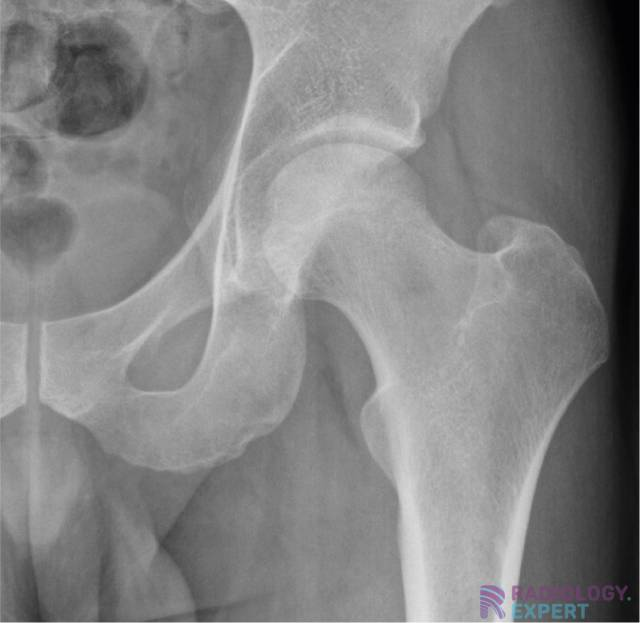

How does the proximal femur look in anatomic position

Femoral necks partially foreshortened

Lesser trochanters partially visible

How does the proximal femur look in internal rotation?

Toes in, heels out

Lesser trochanters not/barely visible, greater trochanters in profile

How does the proximal femur look in external rotation?

Femoral neck greatly foreshortened

Lesser trochanters visible internally

Congenital dislocation of hip

Developmental dysplasia (DDH)

Associated with ischemic necrosis of bone. Ischemia results from poor blood supply to the bone. Affects the epiphyses and may be mistaken for tuberculosis of the skeletal system. Tends to occur in males between the ages of 5 to 10 years and often follows injury to the affected hip. Radiographically the bone in the center of the epiphysis is fragmented and the head of the femur is flattened.

Legg-Perthes Disease